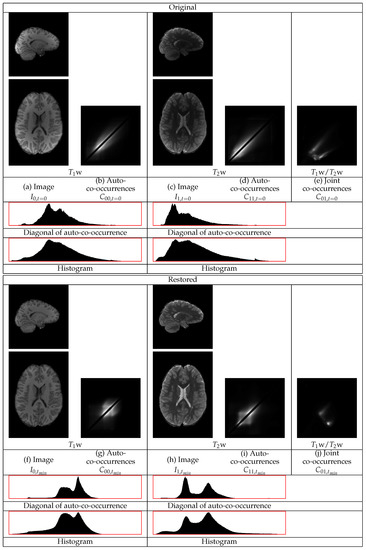

They give the auto-co-occurrences for and the joint-co-occurrences for . The auto-co-occurrences are dominated by their diagonal entries and thus they are weighted down with the sigmoid . The different tissues, or tissues interfaces, of the anatomic images are assumed to correspond to distinct modes of the co-occurrence statistics. An example of the co-occurrences of a pair of and BrainWeb phantom images [37] is in Figure 4. A median filtering is applied to to remove the high frequency noise . The objective of the analysis is to separate the remaining two products in , present in Equation (9) to obtain the factors and , respectively.

Figure 4.

The auto-co-occurrence statistics and the joint-co-occurrence statistics of a and a image of the BrainWeb phantom without non-uniformity, , and with noise of [37]. The densities in the statistics are displayed in logarithmic scale. The individual distributions of the Gray Mater (GM), White Matter (WM), and Cerebrospinal Fluid (CSF) are apparent.

The restorations of the Brainweb phantom images with noise and with the highest level of non-uniformity, , are shown in Figure 5. This figure contains sections from the original and from the restored images as well as the co-occurrence statistics. In this example, the cerebellum in both the w and the w images becomes brighter and thus its statistics become closer to those of the corresponding mean tissue statistics over the remaining image regions.

Figure 5.

The restoration of a w and a w BrainWeb image pair with non-uniformity of and noise of . The restoration makes the cerebellum brighter and the statistics sharper.